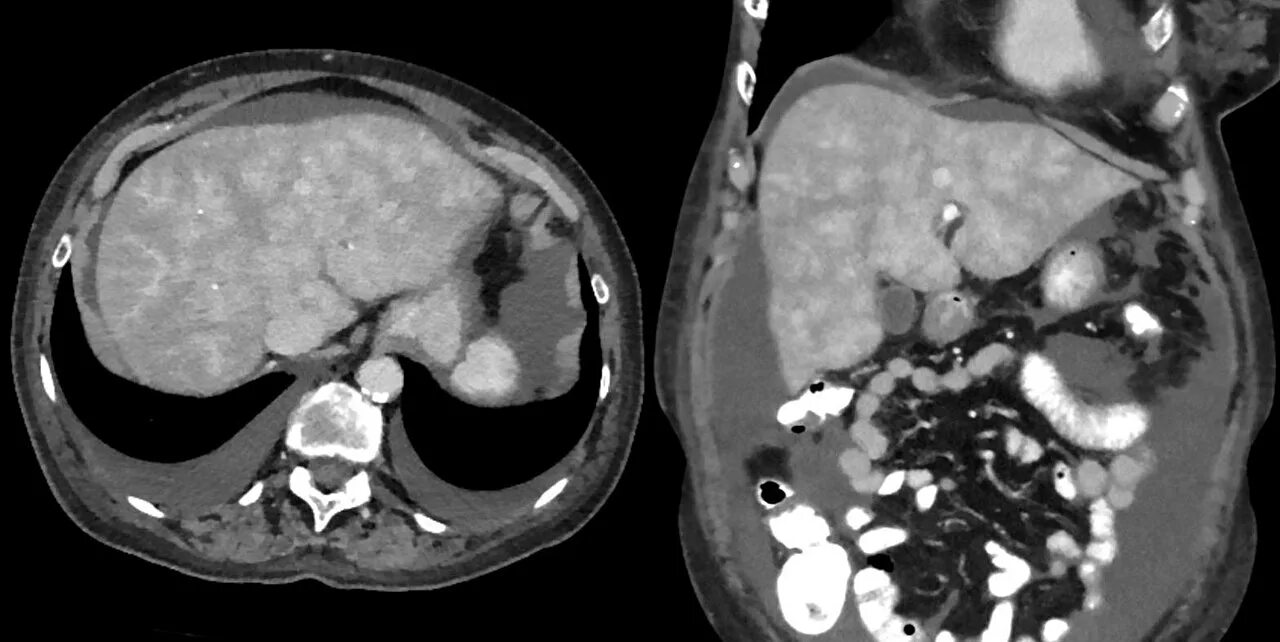

Цирроз печени кт